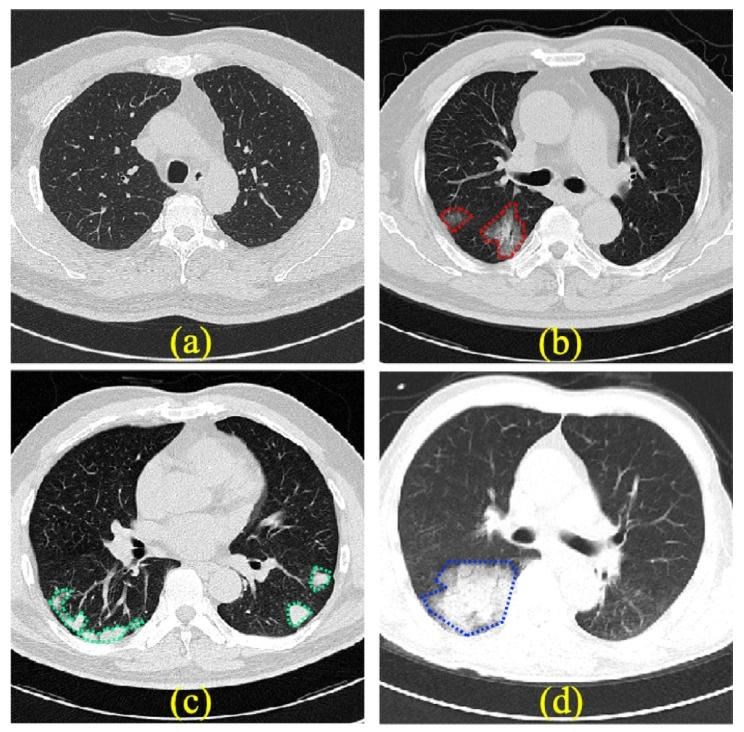

肺部疾病是全球发病率和死亡率最高的疾病之一,包括肺炎、慢性阻塞性肺疾病和肺癌等。肺炎因其高发病率和广泛影响而尤为显著,它是由病毒、细菌或真菌引起的严重感染,对全球数百万人的健康构成重大威胁(Dueck等人,2021)。例如,COVID-19是一种由冠状病毒引起的肺炎,最近肆虐全球,自2019年底以来迅速传播,对世界各地人们的健康造成了严重破坏(Feng等人,2020)。由于肺部疾病(尤其是肺炎)的高发病率和严重性,及时准确的检测对有效管理和干预至关重要。 在临床上,X射线和计算机断层扫描(CT)是疾病诊断、随访评估和病情演变评估中最常用的成像方式之一。与X射线相比,CT筛查因其高分辨率和肺部的三维视图而广受青睐(Fan等人,2020)。图1显示了几种肺炎疾病在CT轴位切片中的感染区域。从CT图像中可以清楚地观察到这些感染迹象,如早期的磨玻璃影(GGO),如图1(b)中的红色区域所示。这表明CT图像可以呈现清晰的病变特征,在肺部疾病检测中具有显著优势。因此,我们旨在开发一种基于CT检查的自动化、准确的筛查和病变检测模型,用于肺部疾病的早期预警。 近年来,由于卷积神经网络(CNNs)在医学图像特征提取方面的优势,许多基于深度学习的算法被提出用于通过CT扫描检测肺部疾病(Qian等人,2020;Wang等人,2020,2021;Harmon等人,2020;Hasija等人,2022)。例如,在CT解读任务中,Qian等人(2020)通过聚合CT切片和体积特征,构建了用于肺炎筛查的多任务多层深度学习系统。Wang等人(2020)通过引入注意力残差模块和多任务损失,构建了基于先验注意力的CT图像COVID-19筛查分类框架。Wang等人(2021)首次提出了用于COVID-19诊断和三维病变分割的联合深度学习模型。 然而,大多数肺部疾病检测模型需要专家标注进行监督,这无疑既耗时又费力。此外,由于难以收集罕见疾病数据,许多深度学习模型无法完全解决正常数据与疾病数据之间的不平衡问题(Gao等人,2020)。通过模型训练能够检测到的异常疾病仅限于那些已知并定义为训练目标的类型。相比之下,异常检测是一种无监督的单类分类任务,它在训练期间对数据分布进行建模,并在测试期间识别具有显著差异的异常。它减轻了对大量标记数据集的需求,并且在检测任何类型的罕见病变方面比监督方法具有更强的泛化能力(Lagogiannis等人,2023)。异常检测模型还允许对具有多个显著病变的数据进行病变可视化(Bercea等人,2022)。 目前,研究人员已经为医学和工业图像提出了许多异常检测方法(Tsai等人,2022;Liu等人,2023;Roth等人,2022;Defard等人,2021;Pol等人,2019;Kimura等人,2020;Li等人,2021)。这些方法主要包括基于重建的方法、基于特征的方法和基于合成的方法。基于重建的方法通常使用生成模型对正常样本的正常性进行建模,并检测测试样本中的偏差。例如,Pol等人(2019)和Kimura等人(2020)使用了一种变分自动编码器(VAE)(Kingma和Welling,2013)变体,该变体迭代地恢复输入图像,直到磁共振成像(MRI)/X射线异常区域被重建为正常区域。然而,如果异常数据与正常训练数据具有共同的组成模式,或者解码器对异常编码具有良好的泛化能力,那么图像中的异常很可能被很好地重建。基于特征的方法将正常特征编码到高维空间中,在该空间中,异常特征将远离嵌入空间中的正常簇。例如,Defard等人(2021)提出了PadiM,通过使用预训练模型和多元高斯分布嵌入来提取异常补丁特征。PatchCore(Roth等人,2022)首先建立了一个代表性的补丁特征库,然后通过计算测试样本特征与库特征之间的距离对输入特征进行评分。然而,由于医学图像的分布与自然图像不同,直接使用预训练可能导致分布不匹配。基于合成的方法通过在正常图像中合成异常来构建二元分类框架。例如,CutPaste(Li等人,2021)提出了一种用于异常检测的简单合成异常生成策略,该策略切割图像补丁并将其粘贴到原始图像的随机位置,从而训练网络区分合成图像和正常图像。然而,合成图像的分布通常无法提前获得,并且很难通过从图像补丁级别进行合成来近似或包含真实异常。目前,尽管CT图像在肺部疾病筛查中非常重要,但利用CT图像进行肺部疾病异常检测的工作却很少。由于其固有的复杂性,该任务面临以下挑战:在CT体积中,二维切片之间的肺区域纹理、大小和位置各不相同,这可能导致正常数据的分布存在较大差异;CT断层中正常数据的肺组织结构与病变区域相似,容易造成误判,难以检测小面积病变。 结合三种异常检测方法的优缺点,考虑到CT图像的固有复杂性,我们提出了一种新的用于CT图像的肺部疾病异常检测和病变定位框架。该框架利用基于重建和合成的方法,并进行了多项改进。所提出的框架使用矢量量化变分自动编码器(VQVAE)(Van Den Oord等人,2017)从训练图像中提取特征并将其存储在码本中。VQVAE可以存储局部特征,使网络能够忽略切片中不同肺大小引起的全局分布差异。提出了一种新的基于无监督特征统计的合成方法,在特征空间而非图像级别合成异常特征,该方法有效地破坏了局部区域的原始特征,提高了基于Transformer的特征分类网络对小区域病变的精确定位能力。此外,我们引入了一种新的残差邻域聚合特征分类损失,鼓励网络根据邻域特征忽略噪声样本的干扰,提高对异常特征的敏感性。我们的主要贡献总结如下: ∙ 提出了一种新的局部显著位置感知异常掩码生成和重建框架,用于CT图像异常检测和病变定位。该框架结合了图像重建和特征合成方法,通过局部异常合成和特征空间中的特征分类实现了准确的肺部异常检测。 ∙ 提出了一种新的基于无监督特征统计的合成方法,在特征空间而非图像级别合成异常特征,有效地破坏了局部区域的原始特征,提高了基于Transformer的特征分类网络对小区域病变的精确定位能力。 ∙ 提出了残差邻域聚合特征分类损失,鼓励网络根据邻域特征忽略噪声样本的干扰,从而提高对异常特征的敏感性。 ∙ 在一个内部CT数据集和一个公共数据集上对所提出的方法进行了严格的定量和定性验证。实验结果表明,所提出的方法在五种肺部疾病的图像级异常检测和病变定位方面优于其他最先进的方法。

Fig. 1. Illustration of different types of pneumonia. (a) A sample of normal CT images;(b) a sample of COVID-19 with ground-glass opacity lesions (red outlined regions); (c)a sample of bacterial pneumonia with consolidation lesions (green outlined regions);(d) a sample of fungal pneumonia with nodular lesion (blue outlined region)

图1. 不同类型肺炎的示意图   (a) 正常CT图像示例;   (b) 新型冠状病毒肺炎(COVID-19)示例,伴磨玻璃密度影病变(红色轮廓区域);   (c) 细菌性肺炎示例,伴实变病变(绿色轮廓区域);   (d) 真菌性肺炎示例,伴结节性病变(蓝色轮廓区域)